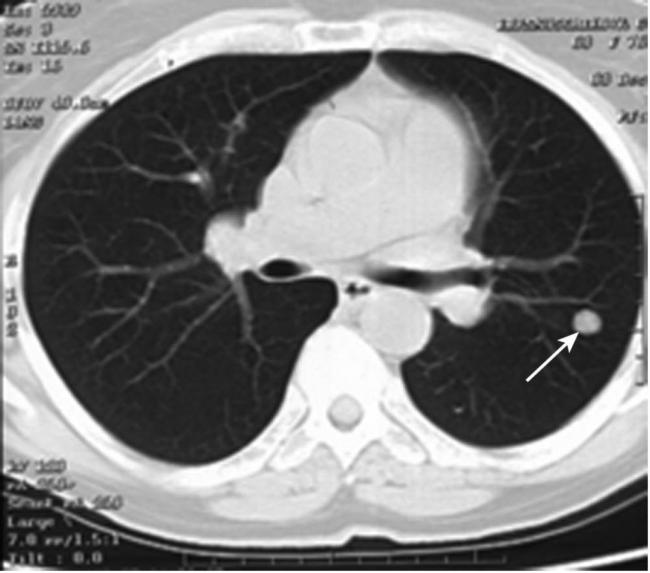

Как очаги в легких выглядят на снимке КТ?

Чтобы человек несведущий смог разобраться в результатах КТ, следует знать о нюансах чтения снимков. Рассмотрим самые актуальные:

- Очаговые образования представляют собой участки белого цвета на черном фоне (на снимке-негативе). В реальности пораженная область, скорее всего, имеет более темный цвет, чем здоровые ткани легкого.

- Если врач заметит на снимке участки кальцинирования или обызвествления (капсул, пропитанных солями кальция) вокруг очага, это может быть признаком доброкачественности образования. Кальцинаты по цвету похожи на кости скелета, видимые на этом снимке. Такие явления часто обнаруживаются после затяжных простудных заболеваний, бронхитов или уже излечененного туберкулеза и представляют собой некий шрам на легких. Пациента с образованием, на котором заметны признаки кальцината, пульмонологи обычно просят раз в полгода делать контрольные снимки.

- В случае, когда образование представляет собой так называемое «облачко» или очаг по типу «матового стекла», требуется более предметное обследование. Внешне оно выглядит как затуманенная область с размытыми границами. В ряде стран пациентам с такими образованиями сразу рекомендуется операция, даже если оно не растет. Уже доказано, что в 80% случаев такие очаги являются предраковым состоянием легких. Альтернатива немедленной операции — постоянное наблюдение с контрольными снимками раз в полгода-год.